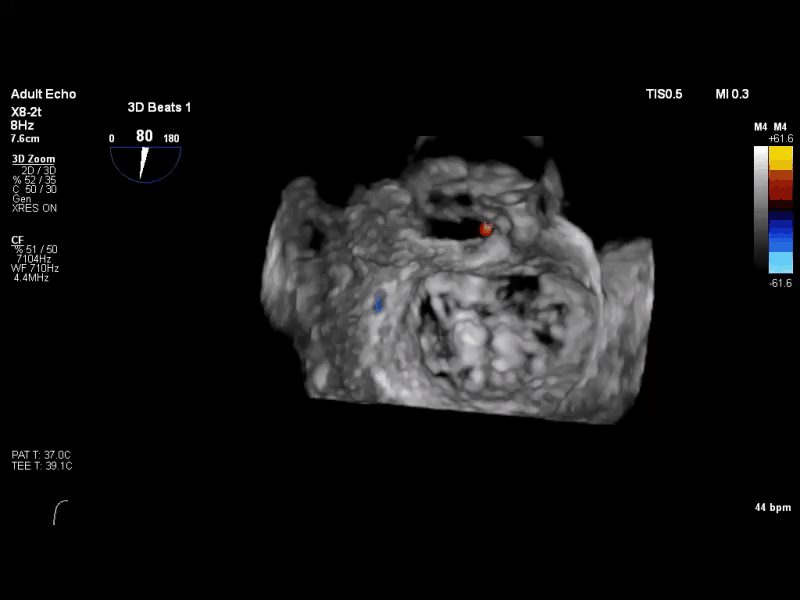

经食道超声心动图(TEE)提示:二尖瓣病变Carpentier II型,DMR,二尖瓣2区反流及P2腱索断裂并瓣叶脱垂,Gap 6 mm,Width 15 mm, 瓣口面积6.7 cm²,2区前叶长20 mm,后叶长19 mm。MR4+,反流束来自于2区,偏心性反流束,指向前叶;VC 11 mm。房间隔穿刺空间约4.5 cm。

术前TEE 3D

术前TEE 3D COLOR